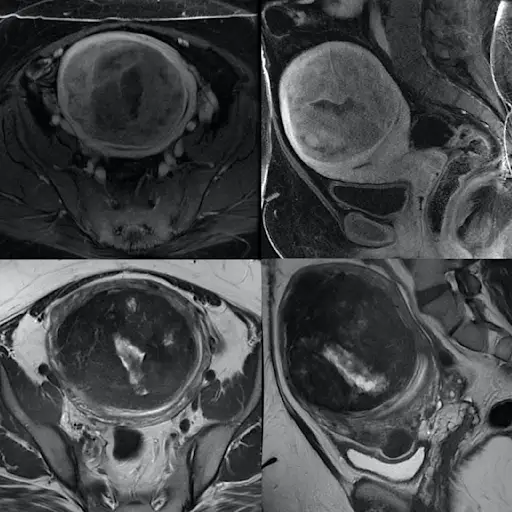

事实:肌瘤有各种形状和大小,可能随着时间的推移生长、萎缩或保持不变。它们会导致大量出血和痛苦的抽筋,而且会变得足够大,从而对你的膀胱和肠道造成压力,导致便秘、尿失禁和性痛苦。但有些女性会否认。“当我看到他们的时候,他们已经长出了巨大的肌瘤。纽约大学朗格尼子宫内膜异位症治疗中心主任、医学博士Kathy Huang说:“有些人会说,‘哦,我本来希望它会消失的,’但他们没有。”

事实:缩小肌瘤的非手术方法包括核磁共振引导的聚焦超声——加热肌瘤直到其蒸发,以及子宫动脉栓塞——阻断导致肌瘤生长的动脉。症状也可以通过治疗来控制,如口服避孕药和含孕激素的宫内节育器。Lager博士同时也是旧金山加州大学旧金山分校综合肌瘤中心的成员,他说:“所有这些都将有助于治疗肌瘤相关的出血,而不改变肌瘤的大小。”

事实:大多数患有子宫肌瘤的妇女即使不切除子宫肌瘤也能成功怀孕。只有一个例外:粘膜下肌瘤——位于子宫腔内的肌瘤。“我们建议在怀孕前摘除这些肌瘤,因为它们会增加流产的风险,”Lager医生说。怀孕还会使子宫肌瘤生长,可能增加骨盆压力。拉格尔博士说,出生后,这些肌瘤通常会再次缩小。